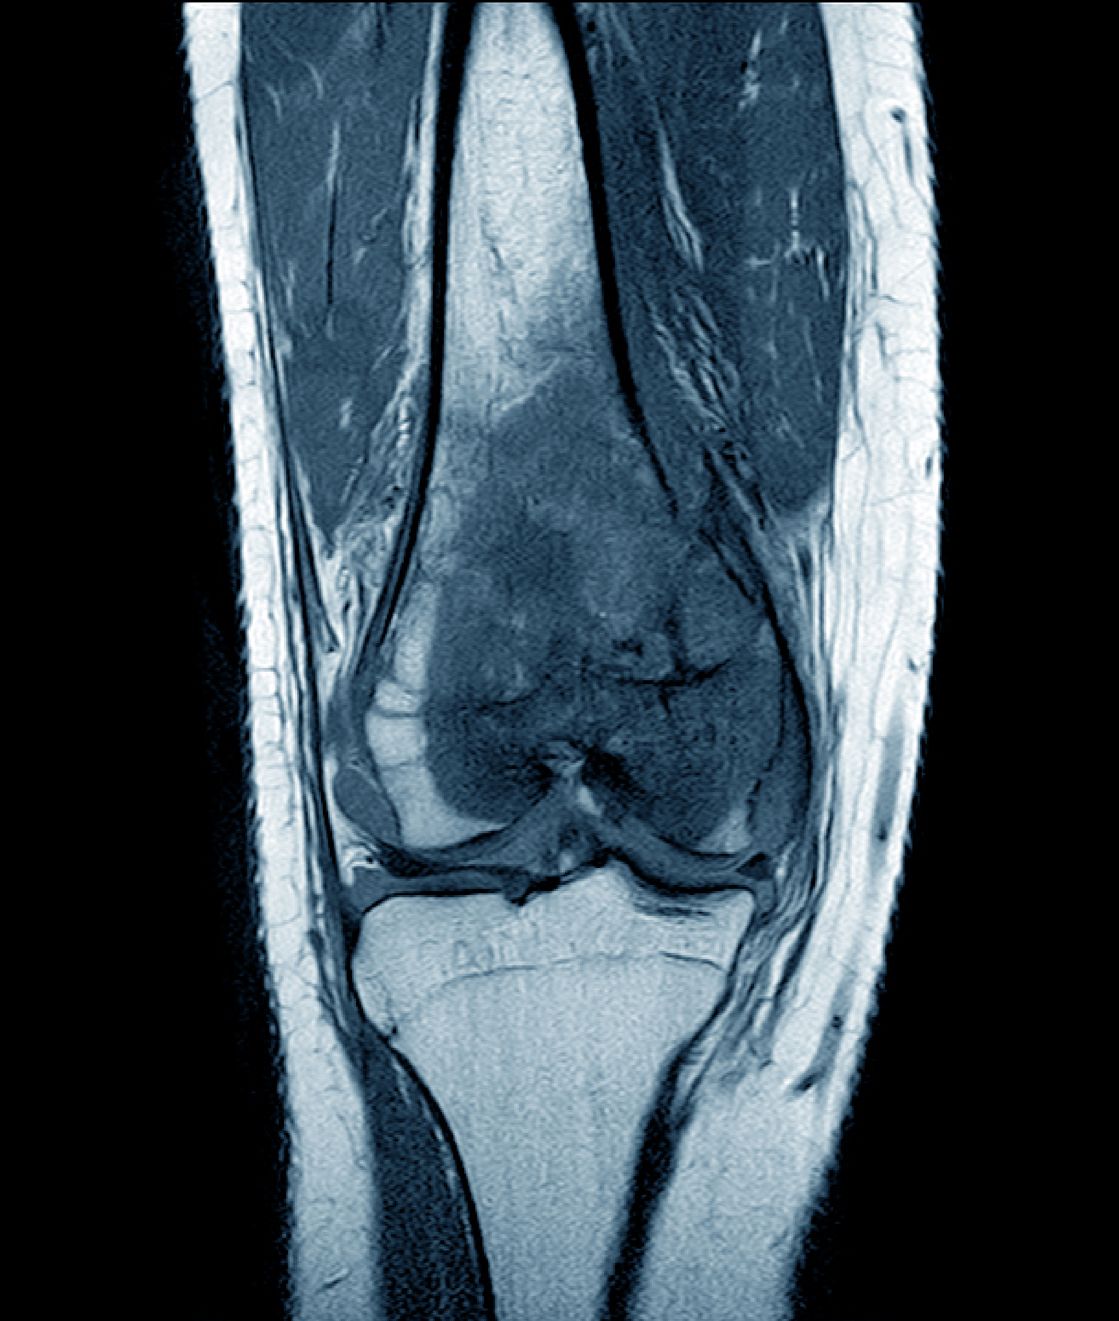

Soft Tissue Sarcomas, Bone Tumors and Gastrointestinal Stromal Tumors (GIST)

Medical Oncology (Dept. of Internal Medicine VIII) is the main department of the German Cancer Society (DKG) certified Center for Soft Tissue Sarcomas, GIST and Bone Tumors (ZWS), which is one of the largest sarcoma centers in Germany and is part of the Comprehensive Cancer Center (CCC) Tübingen-Stuttgart.

At the Sarcoma Center Tübingen we work together with all experts of the University Hospital Tübingen as well as the BG Clinic Tübingen in an interdisciplinary way. Patient cases are discussed weekly on Mondays in the sarcoma tumor conference in the expert group of the ZWS. On this basis, we make important contributions to "personalized oncology" so that we can offer each patient the best individual diagnosis and therapy. A special focus is the generation of molecular genetic profiles (so-called tumor genome sequencing) as well as the facilitation of novel molecular and immunological therapies.